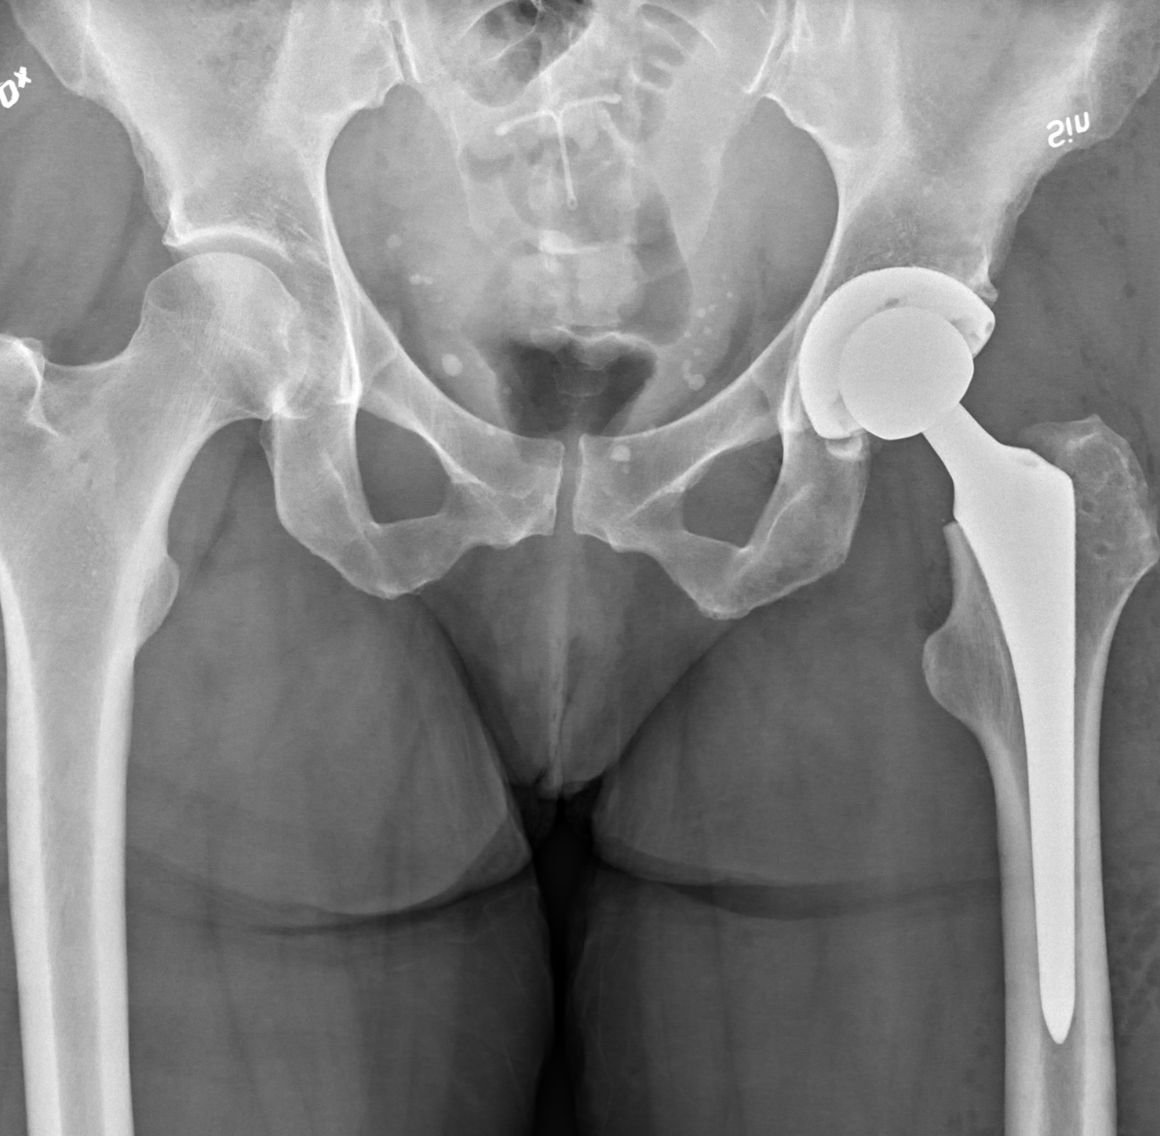

Hip Replacement Surgery involves removing the damaged or worn portions of the hip joint and replacing them with artificial components. This advanced procedure is designed to relieve chronic pain, improve mobility, and enhance overall quality of life. It is highly recommended for patients suffering from severe arthritis, hip fractures, or other debilitating hip conditions that do not respond to conservative treatments.

- Pre-Operative Evaluation: Comprehensive assessments using imaging and clinical evaluations to determine the extent of hip damage and to formulate an individualized surgical plan.